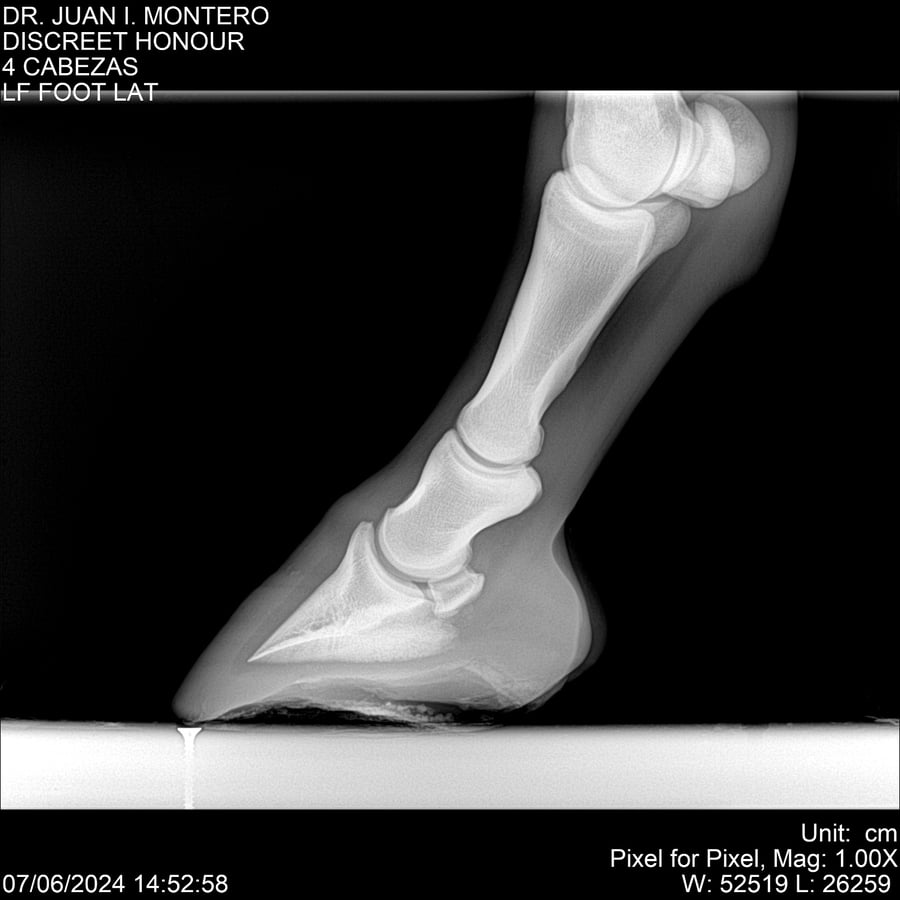

LOTE 6, DISCREET HONOUR 🔥 🔥 🔥 Lote Anterior Volver al remate Lote Siguiente Ficha Contacto Montevideo - Ficha del Lote Identificador: #281093 Categoría: Yeguarizos Montevideo - 82 Visualizaciones ClicData Contacto Empresa: Abelenda N. R., Walter Hugo Nombre*: Teléfono* : E-mail* : Mensaje Enviar Registrese gratis Este contenido Exclusivo está disponible sólo para usuarios registrados Ingresar